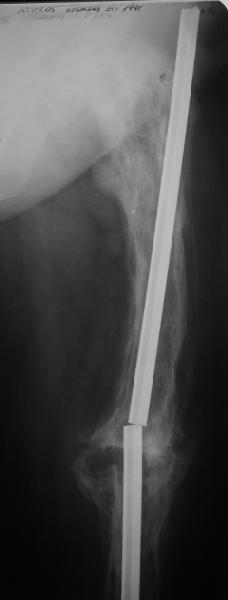

Еще один пример. Пациентка с юга России, прислала рентгенограммы через год. На сегодня прошло 2 г. 8 мес. после операции. Несмотря на не очень убедительный процесс сращения, пациентка ходит. Учитывая остеопороз при Педжете, решили, что динамизировать вообще не нужно.

При переломах на фоне болезни Педжета металлоконструкция часто служит эндопротезом, несущим нагрузку. Динамизация индивидуальна,- по рентген-динамике. Основной упор- на медикаментозную терапию- см. канд. дисс. Колондаева А.Ф.

Анатолий Леонидович Баранецкий совершенно прав. Сращения ждать надо очень долго (несколько лет). Главное - гвоздь попрочнее и потолще. Раньше использовали мощный 4-гранный штифт ЦИТО. Можно и гвоздь с блокированием (блокировать только с одной стороны) - но ни в коем случае не полый. И ходить с тростью. Сейчас в России зарегистрирован очень хороший препарат (с декабря 2006 г.) - Акласта, по 100 мл - обычно хватает 1 (реже двух) инфузии для полной ремиссии (в Белоруссии он появился даже раньше, чем на Украине и в Россиии). Немного хуже Аредия, ее надо в сумме 180-240 мг, полная эффективность 84%. Все в\в кап. бисфосфонаты вызывают выраженную гипокальциемию. Поэтому приходится назначать по нескольку лет альфакальцидол под контролем Са крови (каждые 3-6 мес). Сперва по 6-8 капсул (капель), т.е 1,5-2,0 мкг, затем через 2-4 месяца - по 0,5-0,75 мкг. Препараты Са по 1-2 гр. в день, очень долго.